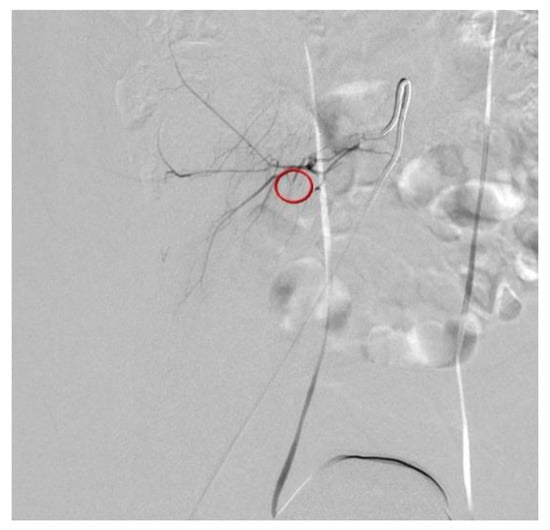

Figure 2. Due to constant abdominal tenderness, flank pain, and tachycardia, selective angiography was performed. The contrast medium was extravasated from the distal fine branch of the right fifth lumbar artery (Figure 2). Selective angiography shows that the contrast medium is extravasated (circle) from the distal fine branch of the right fifth lumbar artery.